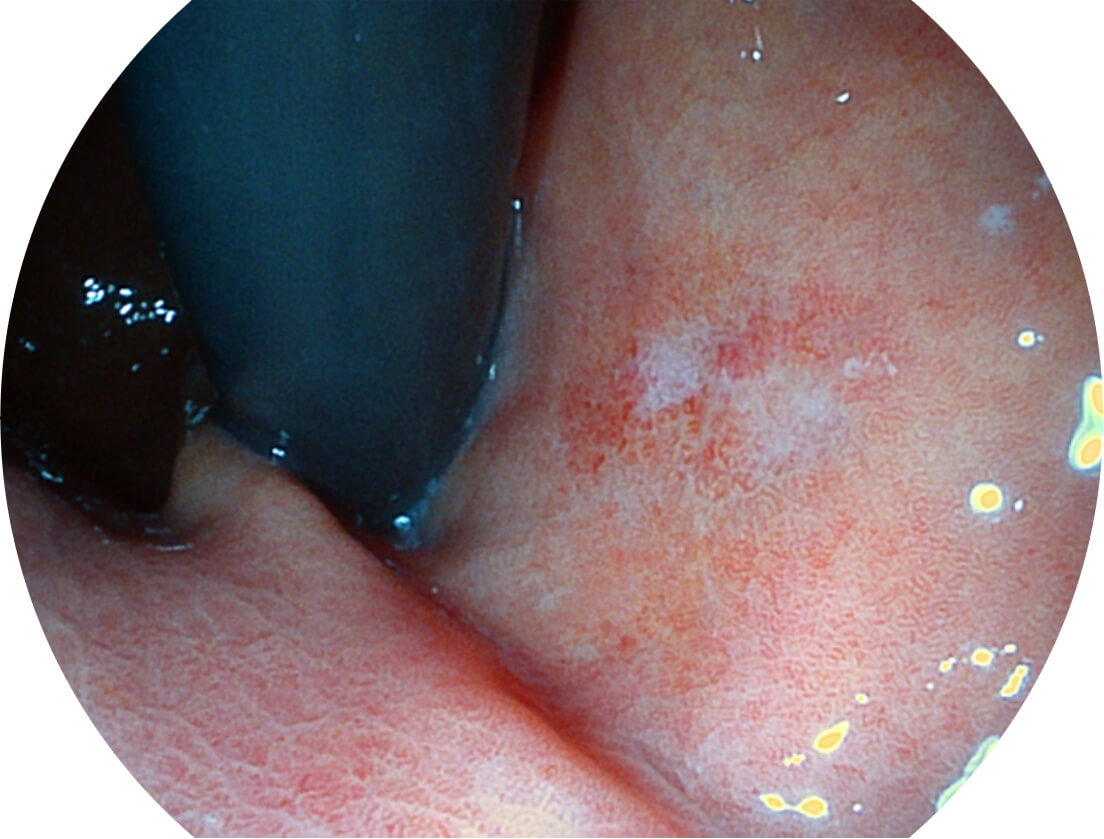

白光图像

SFI图像

图像具有高亮度、高黏膜血管颜色对比度的特点,且不改变粘液、食物残渣、粪便的基本颜色,可在中远景下进行观察,助力消化道早期疾病的诊断。

采用光路合束技术,光谱自由度高,实现了更丰富的照明模式,染色模式SFI及VIST,从远景到近景,助力消化道早期疾病诊断。